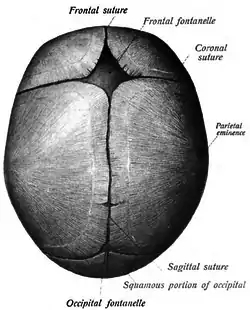

Cranial sutures

The mesenchyme above the meninges undergoes intramembranous ossification forming the neurocranium.[3] The neurocranium consists of several bones, which are united and at the same time separated by fibrous sutures.[3] This allows movement of the separate bones in relation to one another; the infant skull is still malleable.[3] The fibrous sutures specifically allow the deformation of the skull during birth[3] and absorb mechanical forces during childhood[6] They also allow the necessary expansion during brain growth.[3]

In the very first years of life the sutures serve as the most important centers of growth in the skull.[3] The growth of the brain and the patency of the sutures depend on each other.[54] Brain growth pushes the two sides of the patent sutures away from each other, thereby enabling growth of the neurocranium.[54] This means that the neurocranium can only grow if the sutures remain open.[54] The neurocranium will not grow when the forces induced by brain growth are not there.[12] This will occur for example when the intracranial pressure drops; the sutures do not experience stretching anymore causing them to fuse.[17]